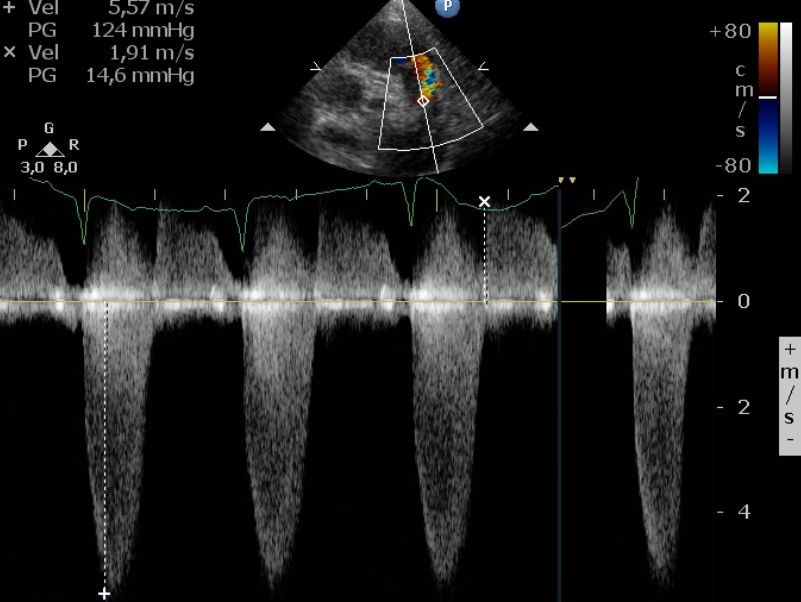

CW (Continuous-Wave) Doppler – Voor hogere snelheden, zoals bij ernstige vernauwingen.

CW-Doppler-echocardiogram

Met een CW-Doppler-echocardiogram kan de dierenarts de bloedstroomsnelheid nauwkeurig meten. In dit geval bleek het bloed in de longslagader veel te snel te stromen (5,57 m/s), wat leidde tot de diagnose ernstige pulmonaal stenose.